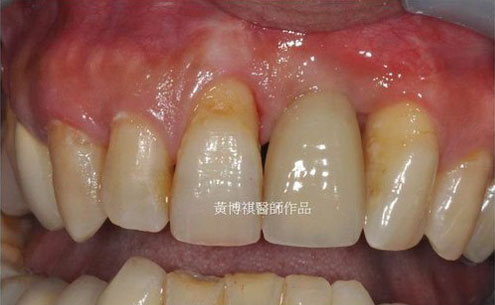

術後完成照。 |